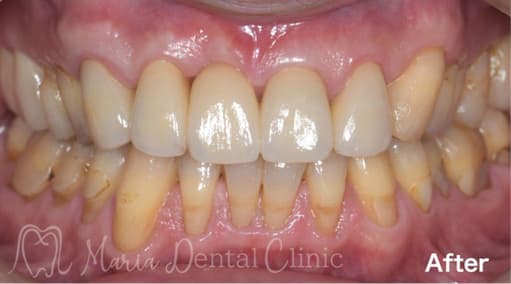

インプラントは、失った歯の部位に人工歯根を埋入し上部に人工歯を装着することで、天然歯のようにものを噛んだり、見た目を美しくすることができます。今後インプラント治療をお考えの方は、まずは、インプラントの特性を知るために、インプラントの構造や具体的なメリット・デメリットを把握する必要があると考えます。そして、ご自身の今後の治療の選択や、インプラントを埋入した後の日々のメンテナンスにその知識を役立ててもらえればと思います。

インプラントの構造について

インプラントの構造の図

インプラントと天然歯は、見た目は似ていますが、構造的には大きな違いがあります。インプラントは人工的に歯の機能を再現したものであり、天然歯とは異なる構造を持っています。

天然歯は歯髄や歯根膜に神経が通っており、温度や圧力を感じ取ることができます。しかし、インプラントには神経や歯根膜がないため感覚が鈍く、強く噛みすぎても気づきにくい、物を噛んだ時に硬い感じがするなどという感覚の違いがあります。強すぎる力がかかると、骨の吸収(骨が減る)などにつながるリスクがあるため、定期的に適切な管理が必要です。